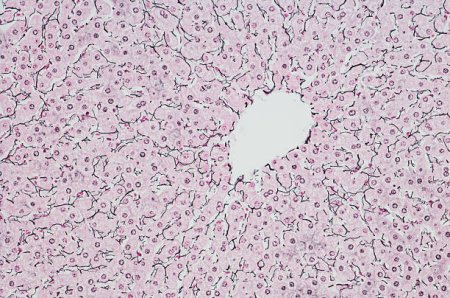

на рисунке представлена микрофотография клетки печени животного для срисовки

Микрофотография клетки печени животного - захватывающий снимок, который открывает перед нами мир мельчайших структур организма. Эта клетка, являющаяся основным строительным блоком печени, обладает удивительными функциями и способностью регенерации. На фото можно ясно увидеть ее уникальную структуру, включая ядро, мембраны и различные органеллы. Изучение таких микромира помогает нам лучше понять работу организма в целом и разрабатывать новые методы лечения и диагностики различных заболеваний.